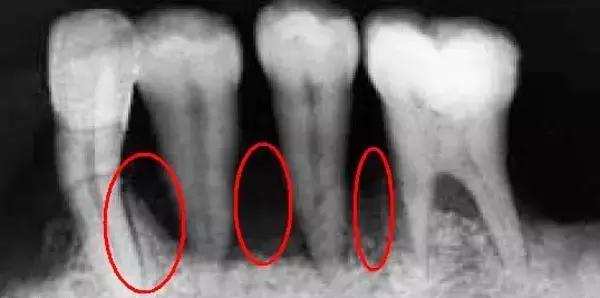

牙周炎

牙周炎是造成牙龈萎缩和牙槽骨吸收的“元凶”之一,而这两者都会导致牙根过多暴露在外。当这种情况发生时,黑三角也就出现了。